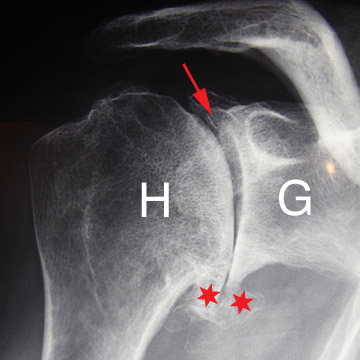

A long terme c’est la pièce glénoïdienne qui pose le plus de problèmes de descellement. Ces descellements se voient sur les radiographies sous forme de liseré évolutif entre la prothèse et le ciment ou entre le ciment et l’os.

Prothèse totale à 10 ans de recul.

Aucun liseré autour de la quille de la pièce glénoïdienne (flèches rouges).

Le liseré sous la surface articulaire n’a pas évolué depuis la pose (flèches vertes).

En cas de descellement ou d’usure, il est parfois nécessaire de réopérer pour sceller une nouvelle pièce glénoïdienne.